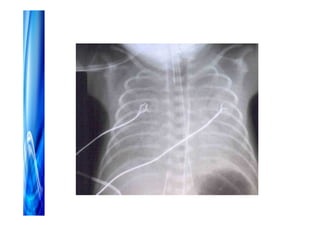

Acesso venoso

• Periférico

• Central PICC